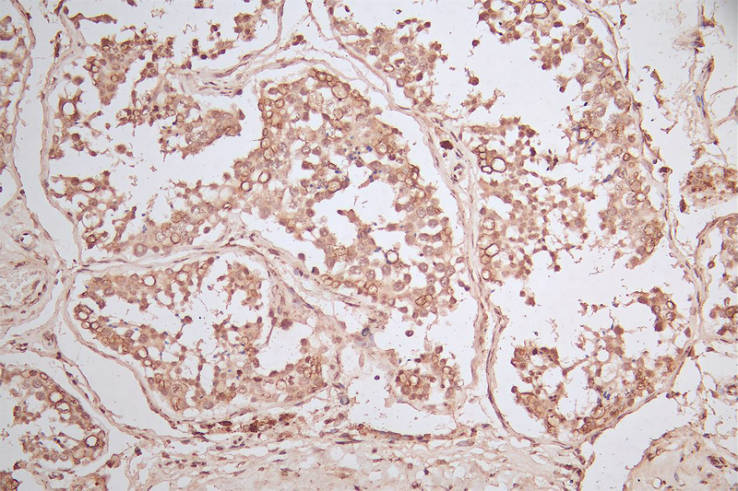

IHC image of CSB-RA007763MA2HU diluted at 1:600 and staining in paraffin-embedded human testis tissue performed on a Leica BondTM system. After dewaxing and hydration, antigen retrieval was mediated by high pressure in a citrate buffer (pH 6.0). Section was blocked with 10% normal goat serum 30min at RT. Then primary antibody (1% BSA) was incubated at 4°C overnight. The primary is detected by a Goat Goat anti-Mouse IgG labeled by HRP and visualized using 0.05% DAB.